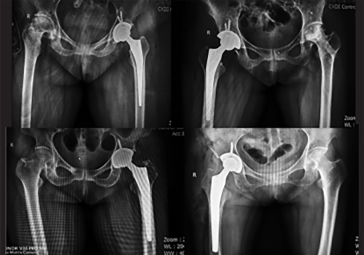

· 髖關節(jié)置換:髖臼+股骨雙側(cè)規(guī)劃

· 制定詳細植入計劃,術(shù)前預演